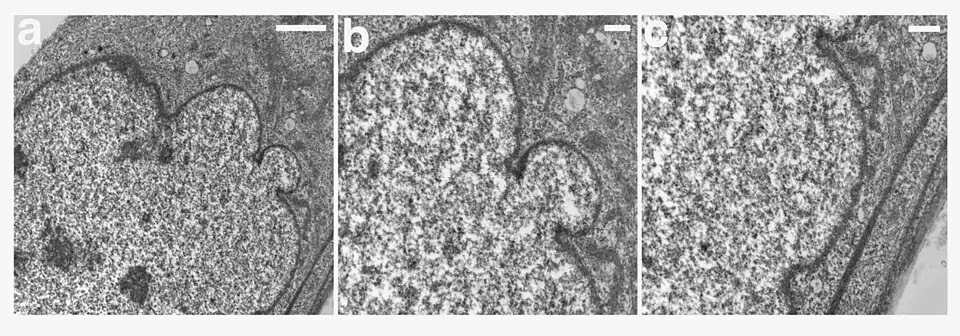

Иллюстрации

.jpg)

_CROPPED.jpg)